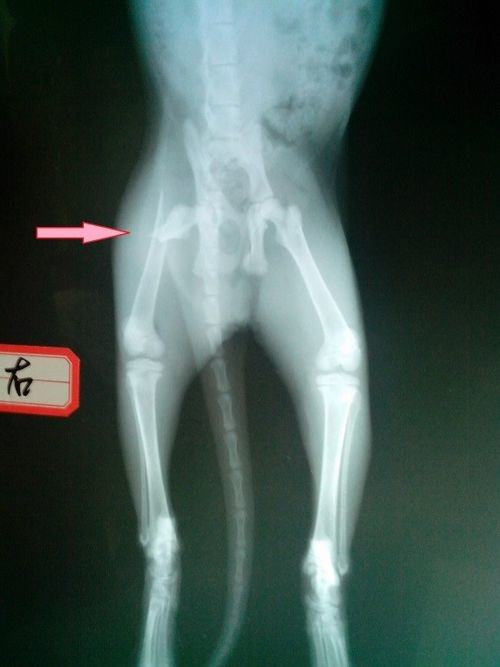

下面介绍病例,患猫名字:小M,品种:美国短毛猫,年龄:三月龄,因玩耍从楼上摔下遂送来医院救治,并未出现内出血等情况,生理以及生化指标均正常。拍摄X光后发现全身三处骨折,分别是左侧肱骨骨折,右侧后肢股骨近端骨折和左侧髋臼窝骨折。下图为猫的骨骼解剖图,红色箭头所示的就是肱骨的位置。

箭头指示为股骨近端斜骨折,箭头对侧可见髋臼窝骨折

由于猫咪比较年轻,骨骼生长较快且恢复能力较强,通过适当的静养髋臼窝处的骨折可以自愈,又由于同时进行三处骨折手术对于身体的损伤很大,所以决定只对股骨和肱骨出进行手术,对于髋臼窝部分采取保守治疗。